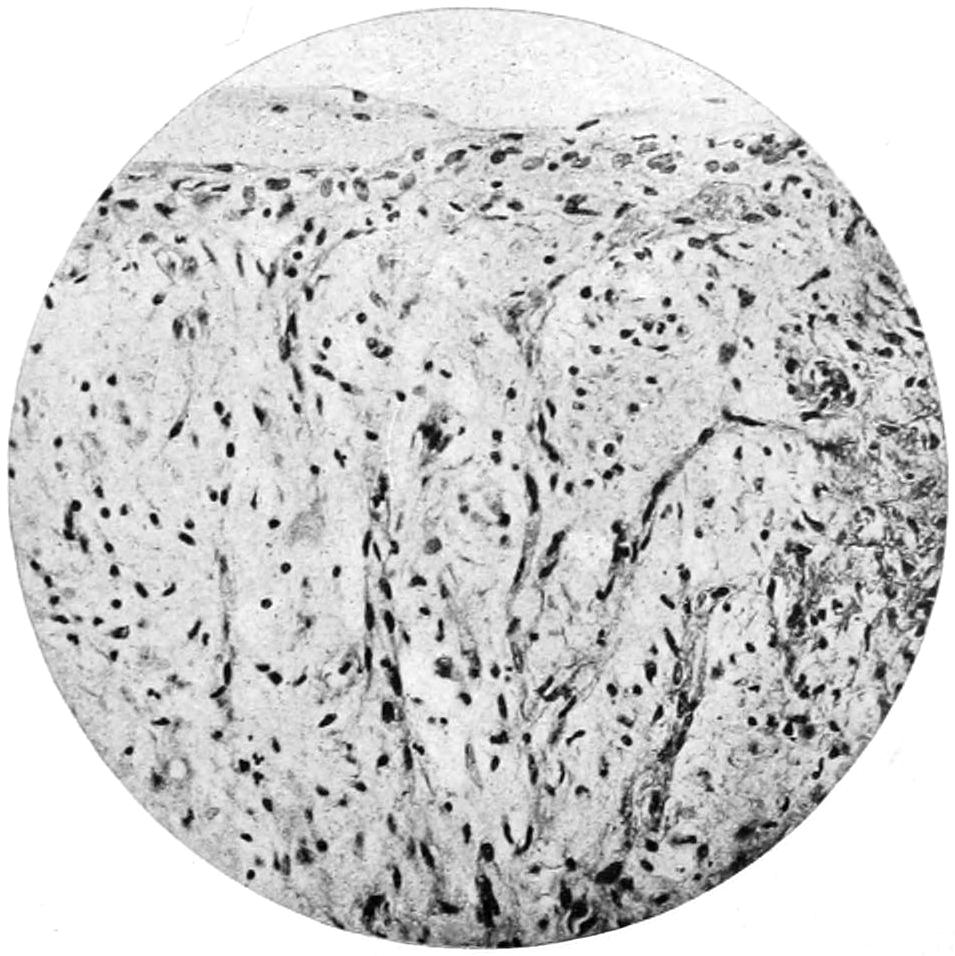

The value of a careful blood examination is well illustrated by Plate I, prepared by Dr. Irving P. Lyon, in which are displayed the alterations of greatest interest to the surgeon.

PLATE I

Fig. I.

Fig. II.

Fig. III.

Fig. IV.

Fig. V.

Fig. VI.

Fig. VII.

Fig. VIII.

DRAWN BY J. N. Z. CHASE

PLATE I.

BLOOD.

(Ehrlich triple stain.)

(Prepared by Dr. I. P. Lyon.)

Fig. I. TYPES OF LEUCOCYTES.

a. Polymorphonuclear Neutrophile. b. Polymorphonuclear Eosinophile. c. Myelocyte (Neutrophilic). d. Eosinophilic Myelocyte. e. Large Lymphocyte (large Mononuclear). f. Small Lymphocyte (small Mononuclear).

Fig. II. NORMAL BLOOD.

Field contains one neutrophile. Reds are normal.

Fig. III. ANÆMIA, POST-OPERATIVE (secondary).

The reds are fewer than normal, and are deficient in hæmoglobin and somewhat irregular in form. One normoblast is seen in the field, and two neutrophiles and one small lymphocyte, showing a marked post-hæmorrhagic anæmia, with leucocytosis.

Fig. IV. LEUCOCYTOSIS, INFLAMMATORY.

The reds are normal. A marked leucocytosis is shown, with five neutrophiles and one small lymphocyte. This illustration may also serve the purpose of showing the leucocytosis of malignant tumor.

Fig. V. TRICHINOSIS.

A marked leucocytosis is shown, consisting of an eosinophilia.

Fig. VI. LYMPHATIC LEUKÆMIA.

Slight anæmia. A large relative and absolute increase of the lymphocytes (chiefly the small lymphocytes) is shown.

Fig. VII. SPLENO-MYELOGENOUS LEUKÆMIA.

The reds show a secondary anæmia. Two normoblasts are shown. The leucocytosis is massive. Twenty leucocytes are shown, consisting of nine neutrophiles, seven myelocytes, two small lymphocytes, one eosinophile (polymorphonuclear) and one eosinophilic myelocyte. Note the polymorphous condition of the leucocytes, i. e., their variations from the typical in size and form.

Fig. VIII. VARIETIES OF RED CORPUSCLES.

a. Normal Red Corpuscle (normocyte). b, c. Anæmic Red Corpuscles. d-g. Poikilocytes. h. Microcyte. i. Megalocyte. j-n. Nucleated Red Corpuscles. j, k. Normoblasts. l. Microblast. m, n. Megaloblasts.